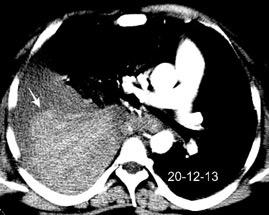

Afectación transdiafragmática: 5,6-43,7% de quistes hepáticos. “Área desnuda” del hígado.

Panda A et al. “Straddling Across Boundaries”. Thoracoabdominal Lesions: Spectrum and Pattern Approach. Curr Probl Diagn Radiol. 2015 Área desnuda. El hígado en contacto directo con el tendón central del diafragma. Contiene el hiato de VCI.